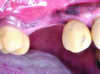

Patient 2: A 63-year-old healthy male patient presented with implant No. 6 exhibiting RPI, having been affected by previously endodontically treated and fractured tooth No. 5 (Figure 3 and Figure 4). The implant had probing depths ranging from 4 mm to 10 mm (Table 1) with the most severe bone loss at the distal aspect of implant No. 6 (Figure 3 and Figure 4).

Fig 3 and Fig 4. Case 2: Initial clinical presentation showing implant No. 6 with RPI, having been impacted by fractured tooth No. 5 (Fig 3); radiograph showing fractured tooth No. 5 with periapical lesion extending to the distal aspect of implant No. 6 (Fig 4).

Fig 4. Case 2: Initial clinical presentation showing implant No. 6 with RPI, having been impacted by fractured tooth No. 5 (Fig 3); radiograph showing fractured tooth No. 5 with periapical lesion extending to the distal aspect of implant No. 6 (Fig 4).